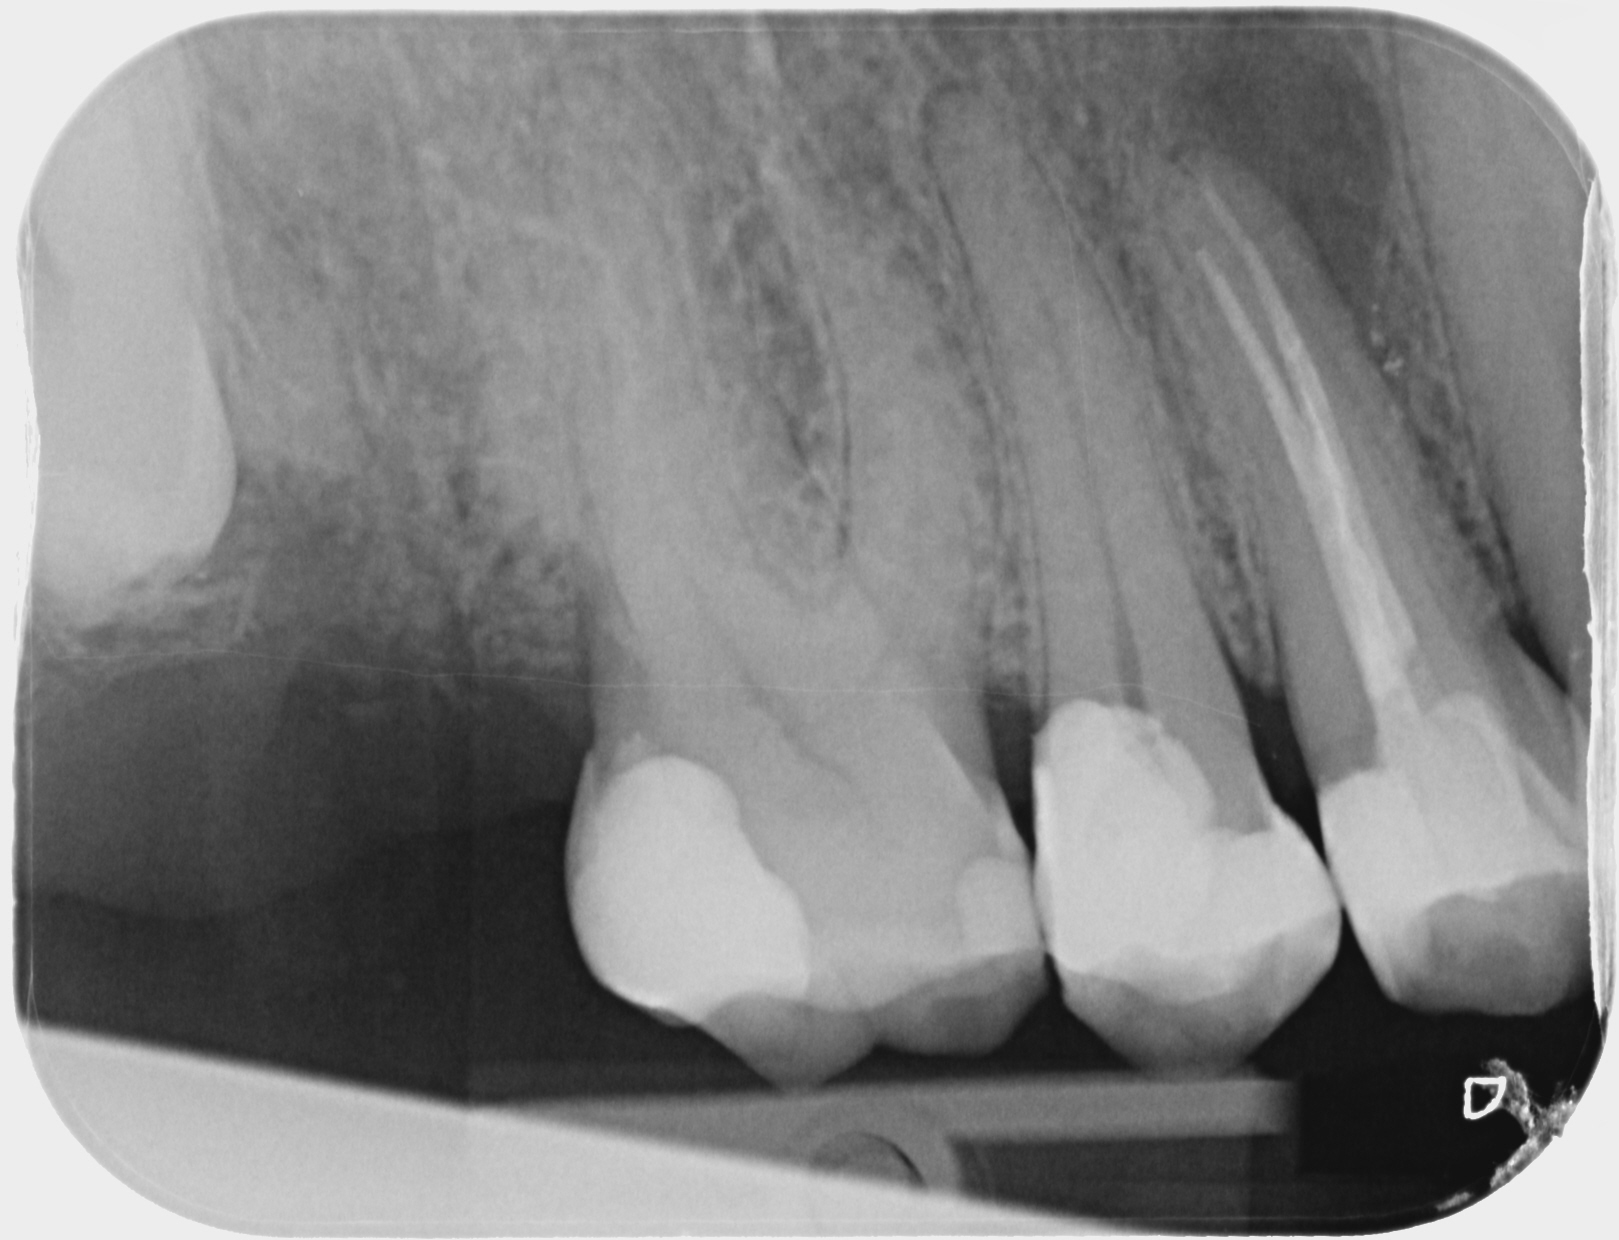

Premolaar met radiolucentie..

]Zoek een oordeel over behandelbaarheid kies op basis van de foto, van premolaar, die bij mij geen pijnklachten geeft, wel abces/bubbeltje met vocht aan punt wortel duidelijk zichtbaar in het tandvlees met voelbaar blaasje aan de punt van de wortel..soms vieze smaak..Zelf vind ik dat kies nog goed is (kroon, geen cariës) IS deze kies nog goed te behandelen ? Zoja, apex of herbehandeling ?

De edentoloog zegt dat tand verloren is en getrokken moet worden ! Wil me niet herbehandelen en zegt dat er een waarschijnlijk een breuk is..verticaal, maar die kan je niet op de foto zien zegt hij. Ik doe nu een antibioticakuur met clindamycine omdat ik erg ziek was afgelopen weekend, en lichte koorts Maar had ook last nog van een verstandskies . HEb nu minder last maar weet niet of ik nu apex resectie moet doen of toch herbehandelen. Wat geeft meer belasting om te genezen ? Kan de kuur voldoende zijn ? Wie me wil herbehandelen mag reageren via een privebericht,.

Als de endodontoloog dit zegt zal het zo zijn. Een fractuur zie je meestal niet op dit soort foto's. Bij onderzoek zal dan meestal een pockets heel lokaal aanwezig zijn. De enige foto die zekerheid geeft is een CBCT scan een dure foto die relatief veel stralingsbelasting geeft.

Een small view cone beam is zeker een goed idee, alvorens de tand te trekken .Met de moderne systemen is de stralingsbelasting zeker acceptabel bij een volwassen patiënt, vooral omdat er toch wel zinvolle info uitkomt in dit geval, om te bepalen of er al of niet een factuur aanwezig is, want dat kan m.i. het verschil wel maken tussen verwijderen of behoud van de tand.